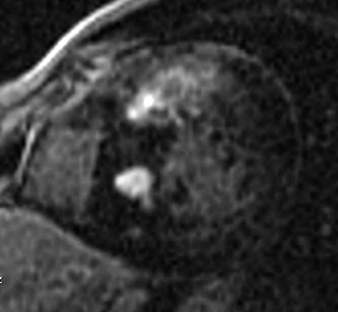

Fig.1., 2.: Hypertrophic obstructive cardiomyopathy: Longitudinal and short axis slices of delayed enhancement of contrast material in the heart: pathologic enhancement is visible in the myocardium in the asymmetrically thickened left ventricular wall, referring to a degenerative-fibrotic process.